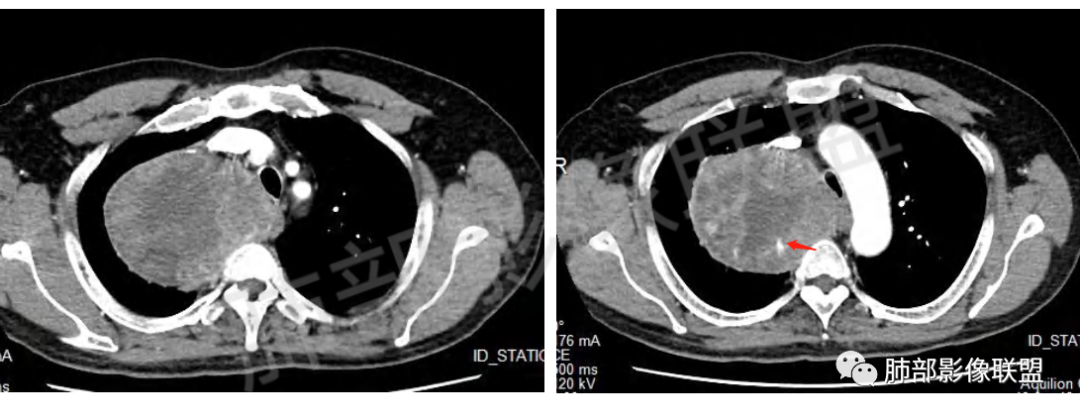

定位肺外,来源于胸膜的SFT(蛇纹状血管)、鞘瘤(不均匀强化,囊变坏死多)、间质瘤(部分层面与食管分界不清)。

肿块把上腔静脉向前部推移,对肺内血管以及气管以推移为主,占位未见肺部血管供血,胸膜掀起处胸膜下脂肪间隙增宽,说明定位在肺外 SFT多为脏层胸膜起源,少部分壁层胸膜起源,壁层胸膜起源SFT不除外,但是胸膜掀起处胸膜下脂肪间隙增宽了,感觉SFT可能性比较小,这样囊变 AB区 纵膈神经起源的神经鞘瘤需要重点考虑,因为CT给的层不够,看不到肿瘤与椎间孔的关系,不敢确定,曾经病理提示高度考虑叶间起源肿瘤,肿瘤细胞呈短梭形细胞构成 不知道和神经鞘瘤是否符合!我重点考虑神经鞘瘤

胸膜来源:孤立,大的边界清,首选SFT

纵隔:上腔静脉后方主要是膈神经,神经源性可以;后方局部与食道关系密切,食道来源肿瘤也可能,一般食道来源向前推移,这里推移方向不支持;气管受压,壁完整,软骨连续,气管单纯受压没有破坏,后方向内推移,不支持气管来源

粗大强化血管,主要看他起源,如果是来源肺动脉,肺内血管供血一是肺内二是脏层胸膜,肺内排除,只剩脏层胸膜SFT;如果这个是纵隔供血,那它可能是神经源性或者壁层胸膜,也可以是SFT比较少

从影像分析:SFT、神经鞘瘤鉴别可能大